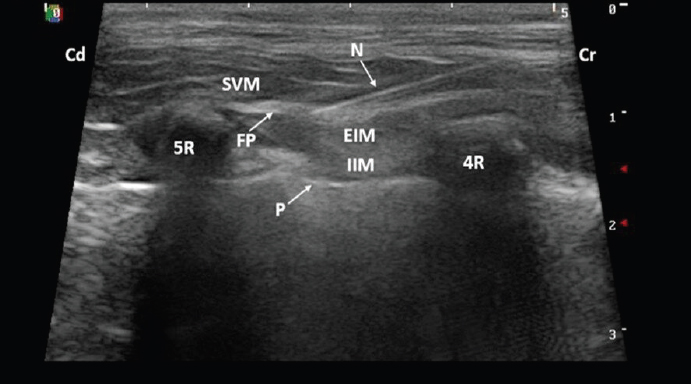

The first case was an 8-year-old male Staffordshire Bull Terrier weighing 22.3 kg diagnosed with a lung tumor. A right-sided thoracotomy was performed at the sixth intercostal space for right caudal lung lobectomy. The dog was premedicated with dexmedetomidine (Dexdomitor®; Orion Pharma, UK) 1 μg/kg and methadone (Comfortan®; Dechra, UK) 0.2 mg/kg IV. Anesthesia was induced with propofol (PropoFlo®; Zoetis, UK) 2.7 mg/kg and lidocaine (Lidocaine Hydrochloride; Hameln, UK) 0.9 mg/kg IV and maintained by total intravenous anesthesia (TIVA) of propofol (Fresenius Propoven®; Fresenius Kabi, UK) at 0.1–0.2 mg/kg/minute. The dog was positioned in left lateral recumbency with the uppermost thoracic limb extended cranially. After clipping and aseptic skin preparation, UGSPB was performed. The linear ultrasound probe (5–13 MHz; SonoScapeTM, Shenzhen, China) was positioned perpendicularly to the long axis of the ribs over the mid-dorsal chest at the level of the fourth and later fifth intercostal space. The plane between the EIM and SVM was identified (Fig. 1). Using a 22 gauge, 38 mm hypodermic needle (Terumo®; Hamburg, Germany), levobupivacaine (Chirocaine®; AbbVie, UK) 0.25%, 1 ml/kg was injected using an in-plane technique. The first injection was performed at the level of the fourth intercostal space and the second at the level of fifth intercostal space (0.5 ml/kg at each site), as described by Drozdzynska et al. (2017). Each time, hydro-dissection of the fascial plane (FP) was seen and interpreted as correct placement of the needle tip.

Fig. 1. Ultrasound image taken with the dog in lateral recumbency with a 5–13 MHz linear probe positioned perpendicular to the long axis of the ribs over the mid-dorsal thorax at the level of the fourth intercostal space. A 22 gauge, 38 mm hypodermic needle was inserted in-plane and advanced cranio-caudally aiming to locate the tip in the FP between the SVM and EIM. (4R): fourth rib; (5R): fifth rib; (Cd): caudal; (Cr): cranial; (EIM): external intercostal muscles; (FP): fascial plane; (IIM): internal intercostal muscle; (N): needle; (P): pleura; (SVM): serratus ventralis muscle.